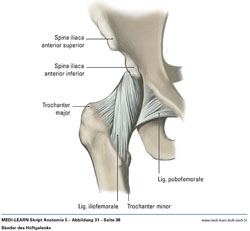

• Bänder des Hüftgelenks